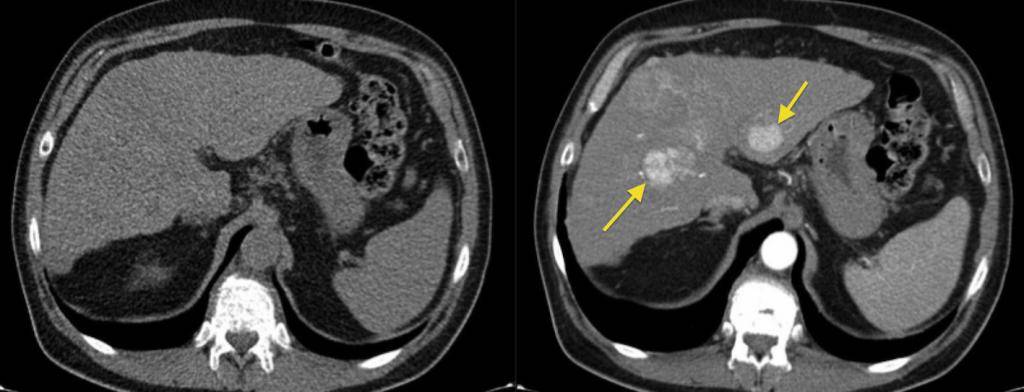

КТ ретроперитонеального фиброза: Изображения и диагностика